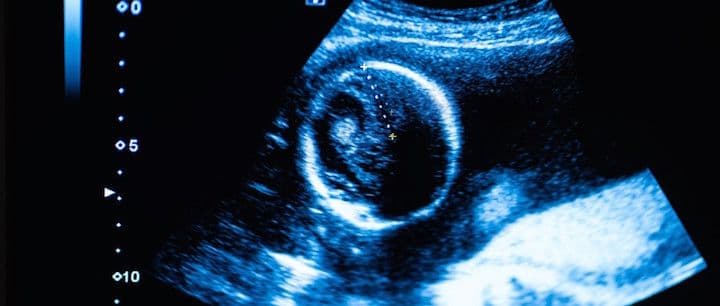

When Is the Earliest an Ultrasound Can Diagnosis Pregnancy?

You may have had a positive pregnancy test but when will you be able to have an ultrasound to confirm the pregnancy?

The first part of the pregnancy that can be seen is the gestational sac. The gestational sac can be seen around cycle days 32-35, which is about 18-21 days after ovulation/fertilization. However, sometimes it can take a couple of days longer to see the gestational sac on transvaginal ultrasound. On abdominal ultrasound, the sac can be seen several days later.

The gestational sac is a structure that surrounds the embryo and can be seen even before the embryo is visible. About 7-10 days later, the embryo can be seen on transvaginal ultrasound (at approximately 6 weeks, 3 days). You can likely now also see the fetal heartbeat.

Usually, you cannot see the pregnancy on a transvaginal ultrasound until a blood hCG level reaches at least 1,500.